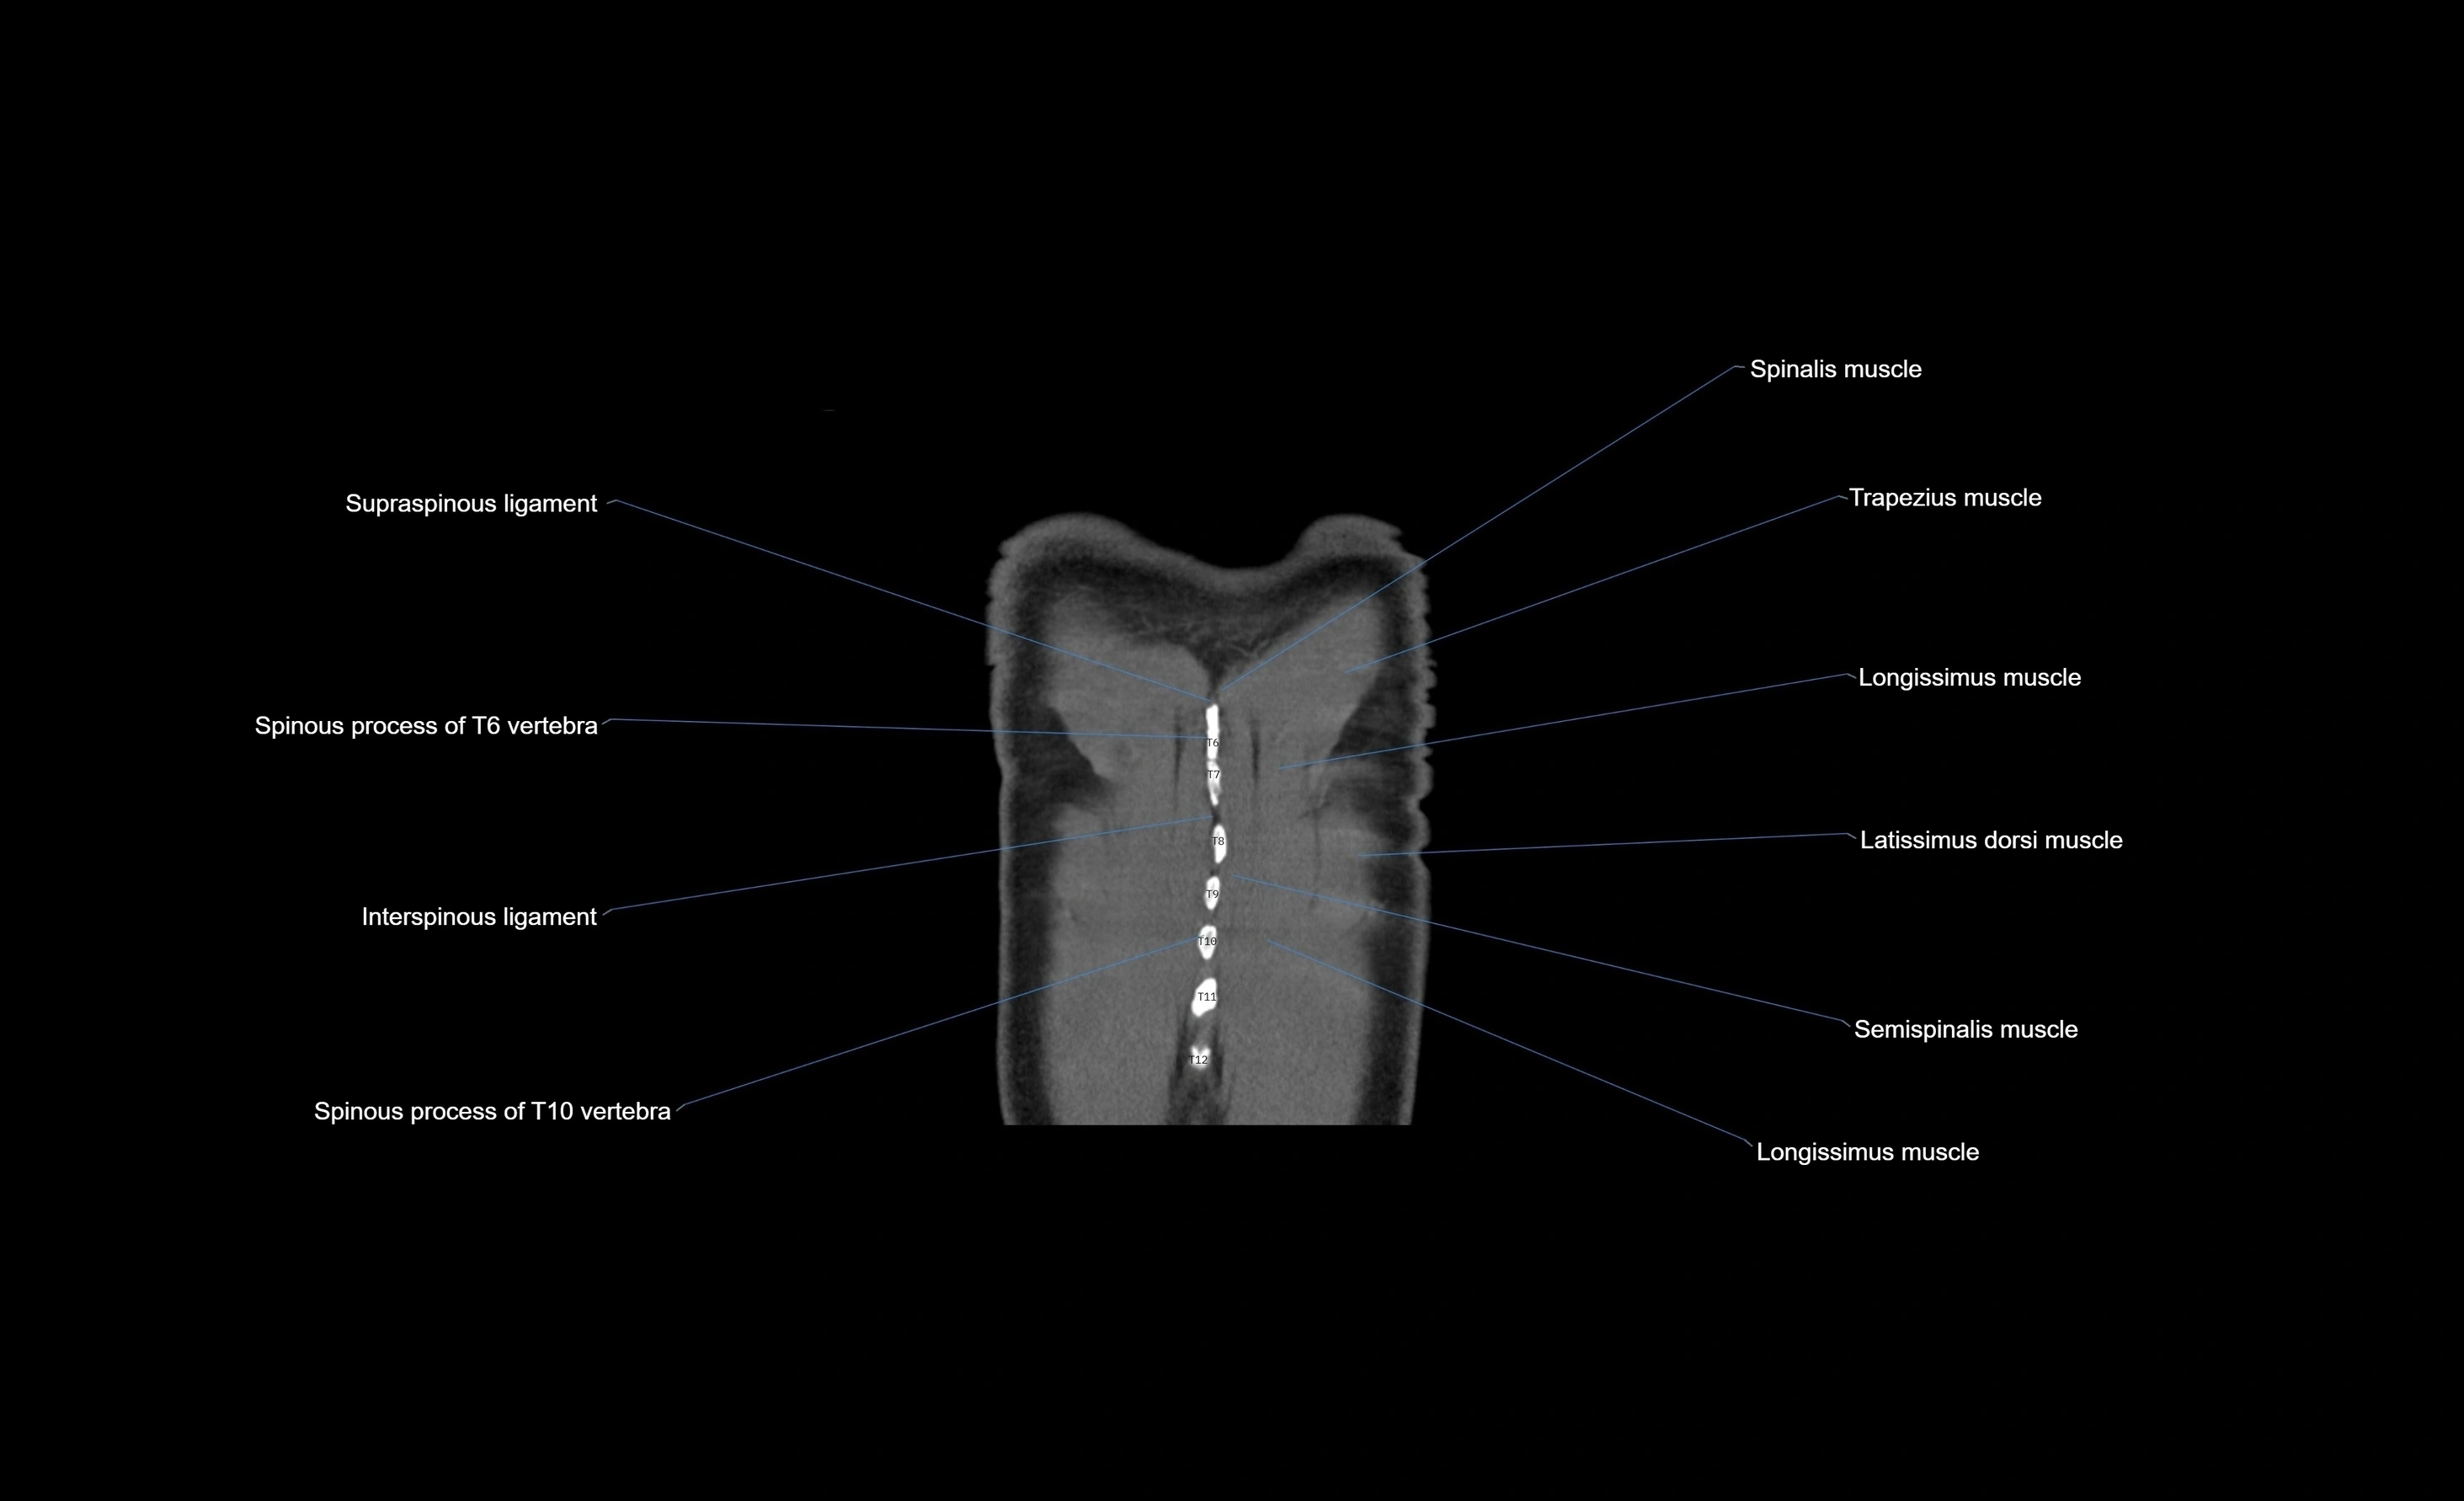

- T (Thoracic spine)